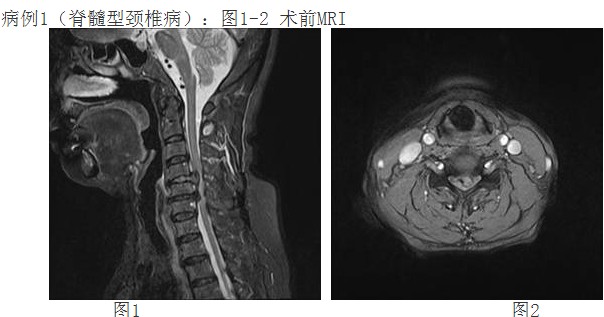

来自惠州农村李阿婆有多年的颈椎病病史,一月前颈部症状加重出现颈痛及四肢麻木、刺痛,不能耐受,上肢手臂力量及握力下降。经人介绍前来我院,经惠州三院脊柱外科谭志宏主任仔细检查,并结合颈椎MRI,明确诊断为颈4/5、颈5/6椎间盘突出症并椎管狭窄,属脊髓型颈椎病。同时认为如果采取保守治疗问题根本解决不了,只有手术治疗才有康复的希望。颈椎手术在脊柱方面属高难度、高风险手术,在外科手术分级中属于最高级别的Ⅳ级手术。

经过谭主任和全科医护人员充分的术前准备和讨论,对患者实施了颈椎前路颈4/5、颈5/6椎间盘摘除、颈5椎体次全切除、椎管减压钛网植骨融合、颈前路钛板固定术。手术取得了成功。术后第二天,李阿婆的四肢麻木就明显减轻,握手能力和手臂力量都明显好转。